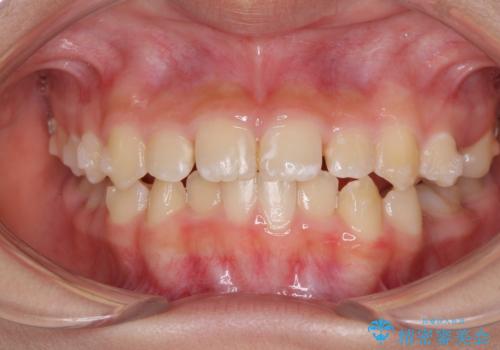

- 小児矯正の頃から診察を行っている患者様です。

上顎骨の幅が下顎骨よりも小さいので、拡大装置により骨幅を広げて上下関係を改善し、その後インビザラインにて歯並びを整えることとしました。

上下の骨幅を改善したことで、スムーズに歯列矯正を行うことができました。